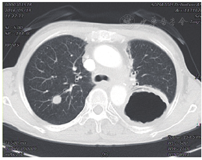

2.胸部CT检查 食管癌术后吻合口增厚,较前基本变化不著;纵隔淋巴结转移治疗后,较前变化不著;右肺结节灶,考虑转移。

患者拒绝行CT引导下肺穿刺,未行化疗联合靶向治疗,于2016年6月行右肺转移灶精确放疗,仰卧位,负压袋固定体位,激光灯摆位,CT扫描,TPS优化放疗计划,IMRT技术,给予右肺转移灶精确放疗,5.0Gy/次,计划10次,总剂量50Gy。危及器官受量:脊髓最大受量4347cGy,心脏平均受量157cGy,右肺平均受量2622cGy,左肺平均受量474cGy,双肺平均受量289cGy,V20=5%(病例22图3)。放疗结束后胸部CT扫描示病变体积明显缩小,近期疗效PR优。放疗结束1个月,再次发现右肺新发转移,并再次给予大分割放疗(50Gy/10次,病例22图4),3个月后病情基本稳定,出现发热、咳嗽、胸闷、憋气,并逐渐加重,CT诊断为急性放射性肺炎(病例22图5),给予甲强龙,氧气吸入,抗感染,雾化等治疗好转后出院,失访。